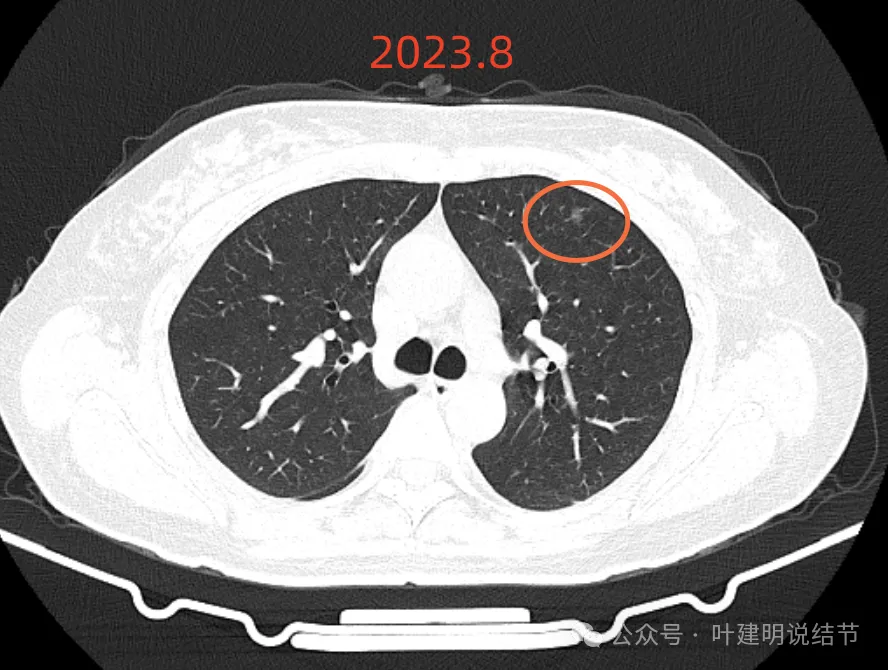

再看2023年8月时复查的影像:

有变化吗?说不上!

点击阅读:问诊分析(2023.9.23):这个于1年多前在国内某著名医院被我叫停手术的肺结节病人,现在怎么样了?